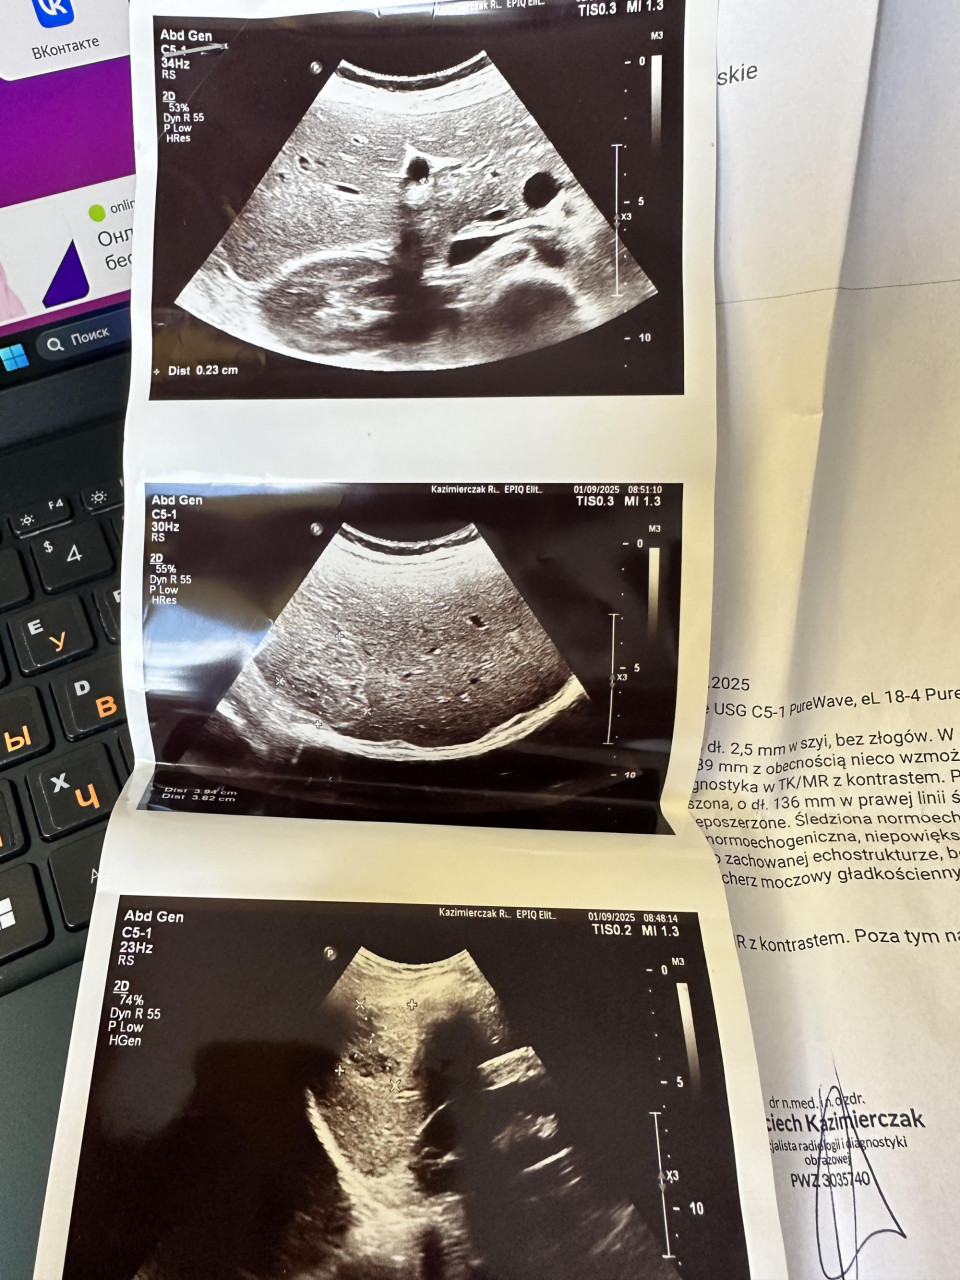

УЗИ

Печень была нормоэхогенной, не увеличенной, субкапсулярно в VI сегменте было видно четко очерченное, вероятнее всего инкапсулированное поражение со смешанной эхогенностью.

(частично изчастично гипоэхогенное), с сегментарно увеличенным кровотоком

по кругу 42 х 35 мм (без прогрессии в размерах по сравнению с предварительным обследованием от 01.09.2025 для дальнейшей диагностики на МРТ), без других четких очаговых изминенийПоджелудочная железа с типичной эхогенностью не увеличена. Селезенка нормоэхогенная, не увеличенная. Брюшная аорта не расширена.